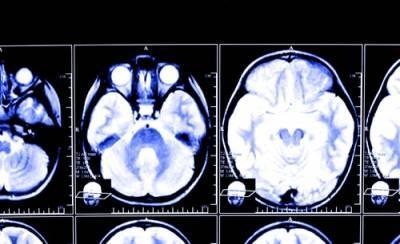

According to a study published in the journal Neurology, even relatively minor brain injuries carry an increased risk of developing Parkinson’s Disease, a neurodegenerative disorder.

Researchers studied 325,870 veterans whose health data was recorded from 2002 to 2014 to explore the correlations between traumatic brain injuries (TBI) and the development of Parkinson’s Disease. Of those who developed Parkinson’s Disease, 65% percent had previously had a TBI ranging from mild to severe in nature.

Parkinson’s Disease is a neurodegenerative disorder that develops gradually and affects movement. The disease causes neurons in your brain to slowly break down or die. Symptoms of the disease include: